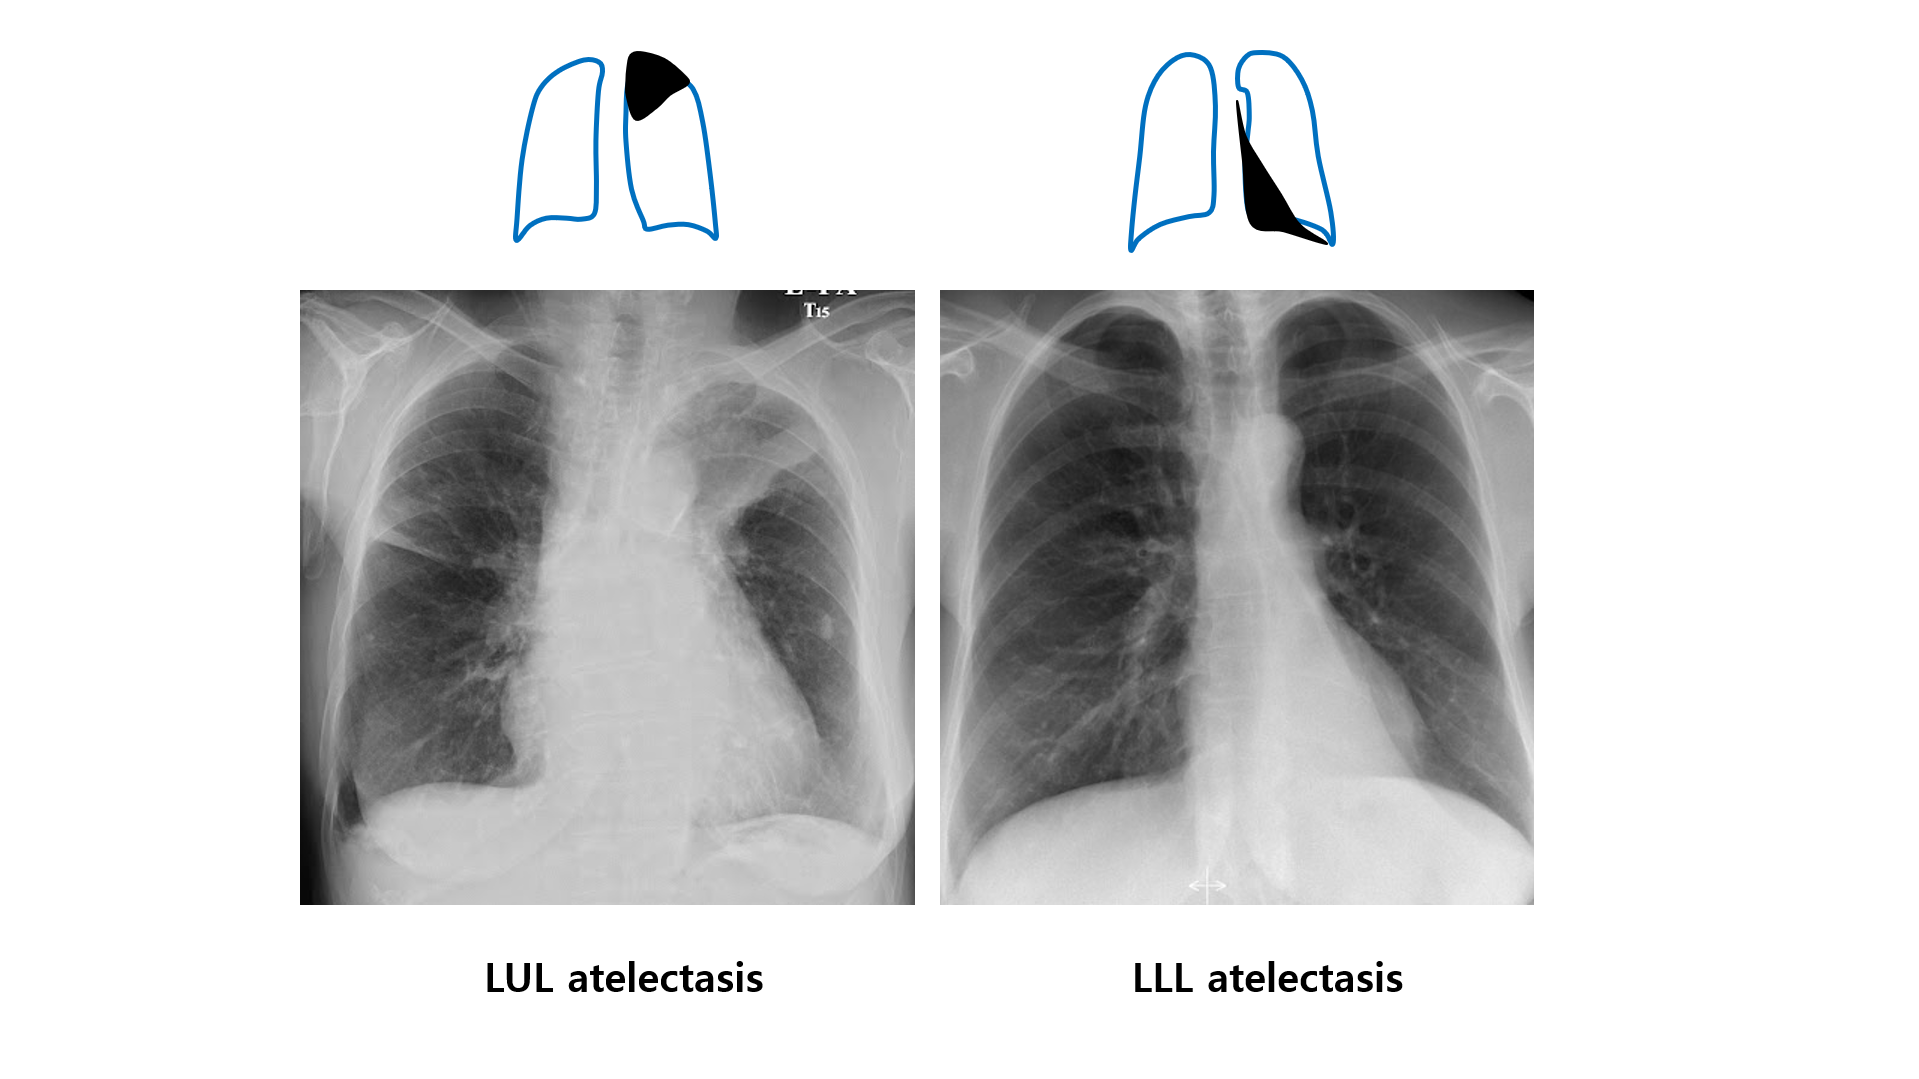

4) 각 lobe의 CXR 소견

(4) LUL 무기폐

• 좌상폐야의 opacity (LLL의 superior segment가 생각보다 위에까지 있으므로 희미하게 보임)

(5) LLL 무기폐

• 좌하폐야의 심장 뒤의 opacity